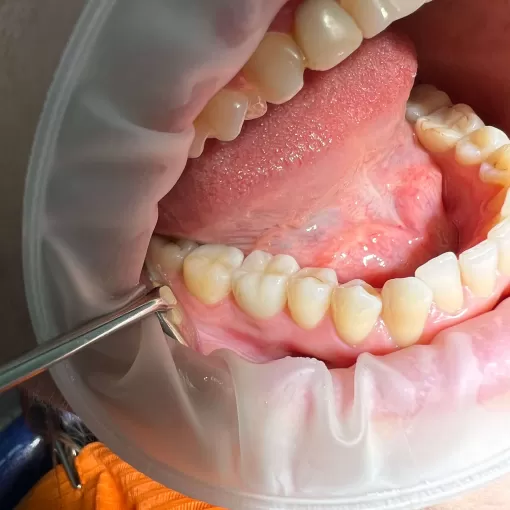

Пациентка обратилась с жалобы на скученность зубов на нижней челюсти и вестибулярное положение клыка на верхней челюсти справа.